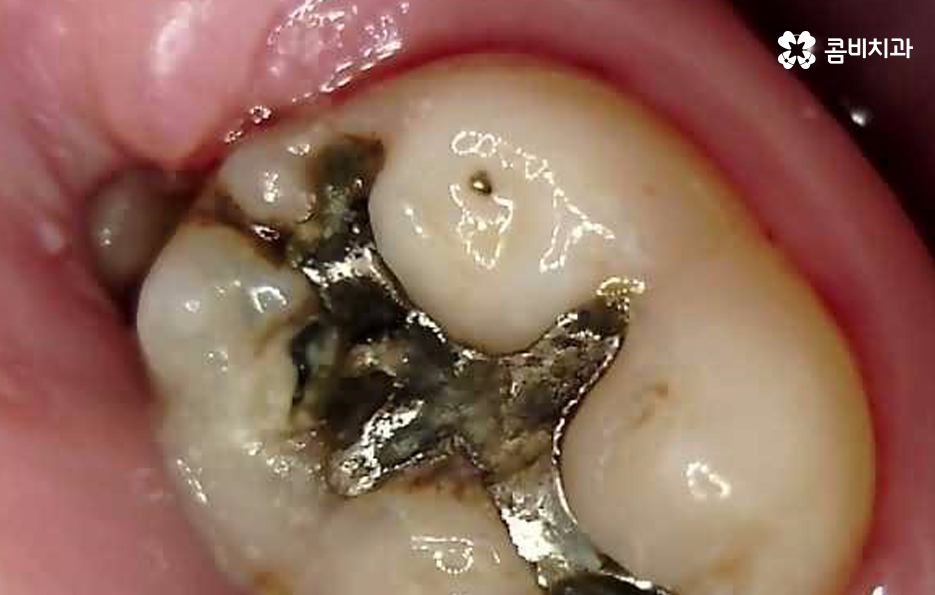

사진에서 보시는 것처럼 이미 과거에 어금니 충치치료 했던 부위에서 보철물 주변이 검게 변색이 되어 있고 보철물에 금이 간 모습도 확인할 수 있는데요

어금니 충치치료 후에도 꾸준히 보철물 상태를 확인하면서 2차 충치의 우려가 없는지 주기적으로 검진해야만 필요한 경우 보철물의 교체와 재치료를 통해 자연치아의 수명을 보존할 수 있어요

많은 분들이 오래된 보철물로 인해서 2차 충치의 문제가 발생되고 있으며 보철물 안에서 발생한 2차 충치의 경우 눈으로 확인이 어렵다는 점에서 아플 때까지 참다가 치료 시점을 놓치는 경우도 많을 거예요

오늘 소개드린 환자분의 케이스는 사랑니 만의 문제라고 보긴 어렵고 오래된 보철물로 인한 2차 충치로 볼 수 있으며 새로운 보철물로 어금니 충치치료 다시 해야하는 케이스로 볼 수 있는데요